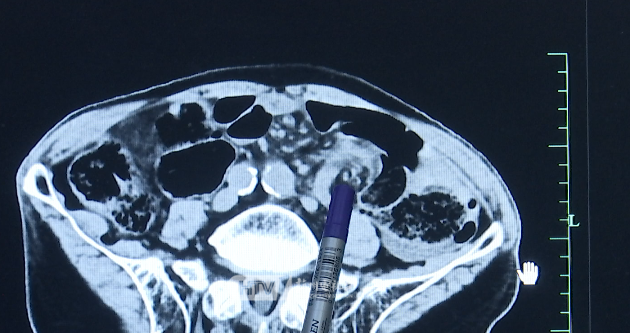

据此前报道,89岁的孙大伯,平时身体比较硬朗,偶尔会犯便秘。周六晚上,家里煮了一大锅汤圆,孙大伯吃了三颗,没想到半夜他突然腹痛剧烈,且有便血情况。家人紧急送他到医院就诊。医生触摸患者腹部发现有鼓胀,安排了腹部CT。

病理报告证实,他乙状结肠扭转的“元凶”正是汤圆。医生提醒,肠扭转是常见的外科急腹症,严重的会有生命危险。如果我们把肠道看做是一条公路,食物就是经过的车辆,难以消化的糯米、淀粉类食物就像移动缓慢的老爷车,不仅容易造成“肠道拥堵”,还容易导致肠蠕动加快。尤其对于老年人和有便秘病史、腹部手术史或其他肠道疾病史的高危人群,会明显增加肠扭转、肠梗阻、肠套叠的发生率。